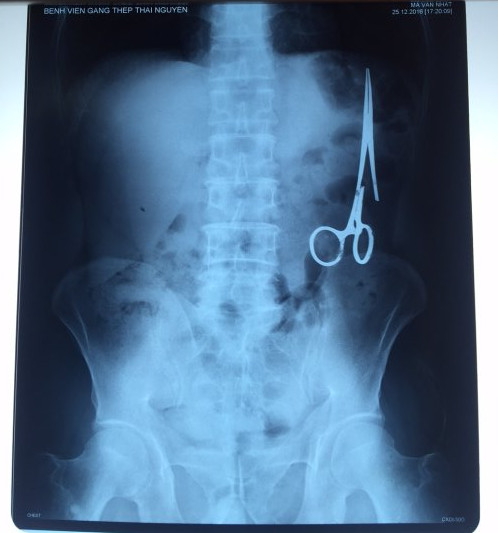

遺留在病人腹中的剪刀

據(jù)越南青年報1月2日報道,在越南首都河內(nèi)醫(yī)療專家的幫助下,越南東北部的太原?。═hai Nguyen)鑄鋼醫(yī)院的醫(yī)生日前從54歲患者M.V.N腹中取出一把醫(yī)用剪刀。這把剪刀是此前曾為M.V.N手術(shù)的醫(yī)生遺留的,已經(jīng)在其腹中待了18年時間。

醫(yī)務(wù)人員表示,這把剪刀遺留在病人腹部左側(cè),與結(jié)腸緊挨著。剪刀的把手已經(jīng)生銹,部分器官也已經(jīng)與剪刀粘連起來。但在過去多年中,M.V.N沒有任何不適感覺,也從未因為留在腹中的剪刀引發(fā)的相關(guān)問題去看過醫(yī)生。直到2016年12月,M.V.N因為遭遇了一場車禍,才到鑄鋼醫(yī)院進行身體檢查。

超聲波檢查顯示,M.V.N的腸子中有個奇怪物體,看起來就像醫(yī)用剪刀。M.V.N證實,他曾于1998年6月份在北江省綜合醫(yī)院接受手術(shù),在此后也從未進行過任何手術(shù)。近來,他感到腹部有些疼痛,并試圖通過服用藥物治療。12月27日,M.V.N回到北江省綜合醫(yī)院再次進行超聲波檢查,顯示其腹部的確存在怪異物體。

越南衛(wèi)生部要求北江省綜合醫(yī)院對此事進行調(diào)查,查找當(dāng)年為M.V.N做手術(shù)的醫(yī)務(wù)人員,并呈報調(diào)查結(jié)果。但北江省綜合醫(yī)院表示,醫(yī)院只會保存病人的醫(yī)療記錄15年。因此,很難確定當(dāng)年到底是誰為M.V.N實施手術(shù),更難查證責(zé)任人。